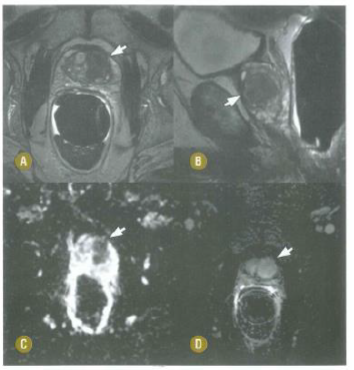

Paciente de 30 anos procura pronto

atendimento por dor testicular à direita com

início após contusão em partida de futebol.

Nega disúria e febre. Diante do quadro do

trauma escrotal, é correto afirmar que

Paciente de 71 anos com aumento do PSA realiza RM com o seguinte resultado. Sobre essa RM, é correto afirmar que